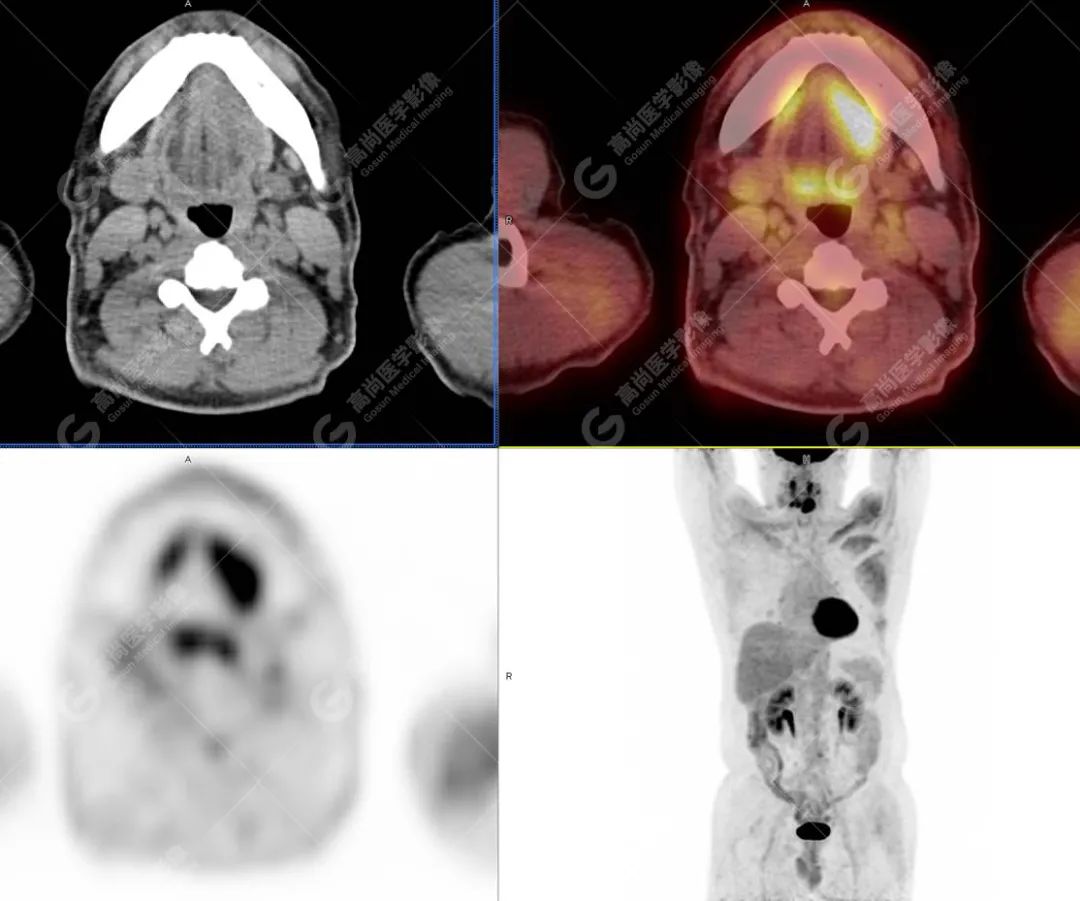

PET/CT影像图

图1

影像诊断: 1.舌体部左右侧软组织明显增厚,密度稍低,左侧为著,代谢异常增高, 考虑为舌癌,并口底受侵, 建议穿刺病理学检查明确。

2.双肺多发大小不等实性结节,部分代谢轻度增高, 考虑为转移瘤。